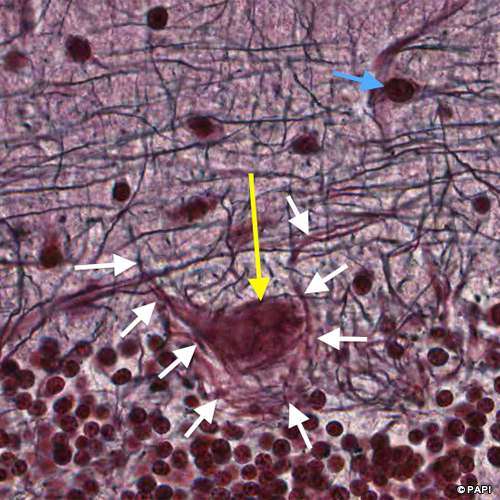

Yellow arrows indicate the Purkinje cells. Blue ones indicate the nuclei of the Bergmann glia, which is the astrocyte in the Purkinje cell layer. A white arrow points the basket cell in the molecular layer.

The Purkinje cell (a yellow arrow) is surrounded by the axon (white arrows) of the basket cell (a blue arrow).